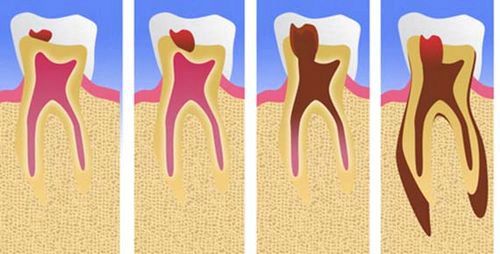

Насамперед захворювання завдає удар по специфічної тканини, яка називається -цемент зуба-. Це кістка, яка покриває корінь і шийку і забезпечує надійне кріплення зубів в лунці. Потім поразку вже переходить на корінь, який розташований в альвеоли. Усередині нього знаходиться канал, заповнений пульпою. Через канал в зуб входять нерви, а також артерія. Як ви бачите, корінь - надзвичайно важлива частина зуба.

Ускладнення карієсу В більшості випадків перехід від каріозного плями до глибокого карієсу займає 1-4 роки, але у пацієнтів з сприйнятливою емаллю процес займе всього 3-4 місяці. При ускладненні карієсу виникають гострі короткочасні болі, підвищена чутливість емалі, неприємний запах з рота.